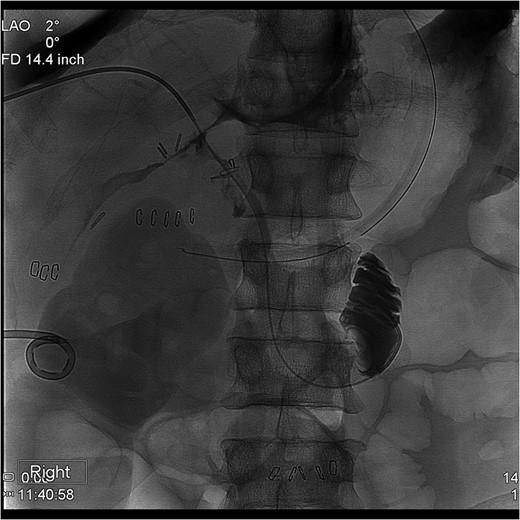

The PTC study confirmed the presence of a completely transected duct, and, fortunately, the ductal injury was traversed with a wire with entry into the distal ductal orifice and into the duodenum (Figs 4–6). Following the procedure, the patient was taken directly to the operating room for open surgical repair.

Percutaneous Transhepatic Cholangiogram showing contrast filling the distal duct following continued injection.